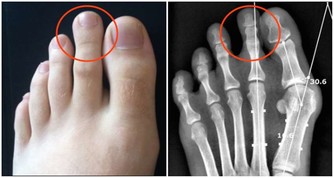

先說“痛”字,主要是發病時患者的關節會產生劇痛,就像身體的某個部位長出刺來一樣,想想就內心就覺得疼啊!再說“風”,這說明痛風也就是痛一會兒,時間不是很長,就像一陣風刮過之後,就沒了!